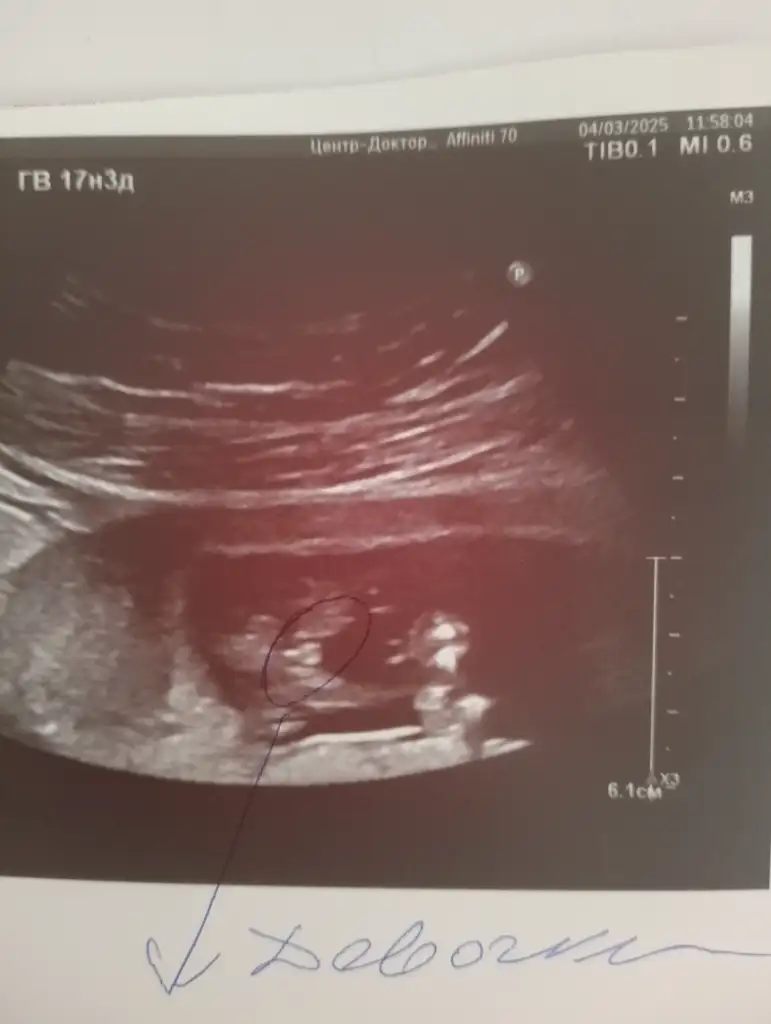

Merhaba onun nub teorisine göre çıkıntısı paralel durduğu için kız diye tahmin ettim,sizin görüntü karından alındıysa ramzi teorisine göre erkek duruyor6 haftalik tahminde bulu

Sizin görüntüyü göremedim atar mısın bi dahaBende çok merak ediyorum sağlıklı olsun tabi bana da tahmin yapabilirmisiniz